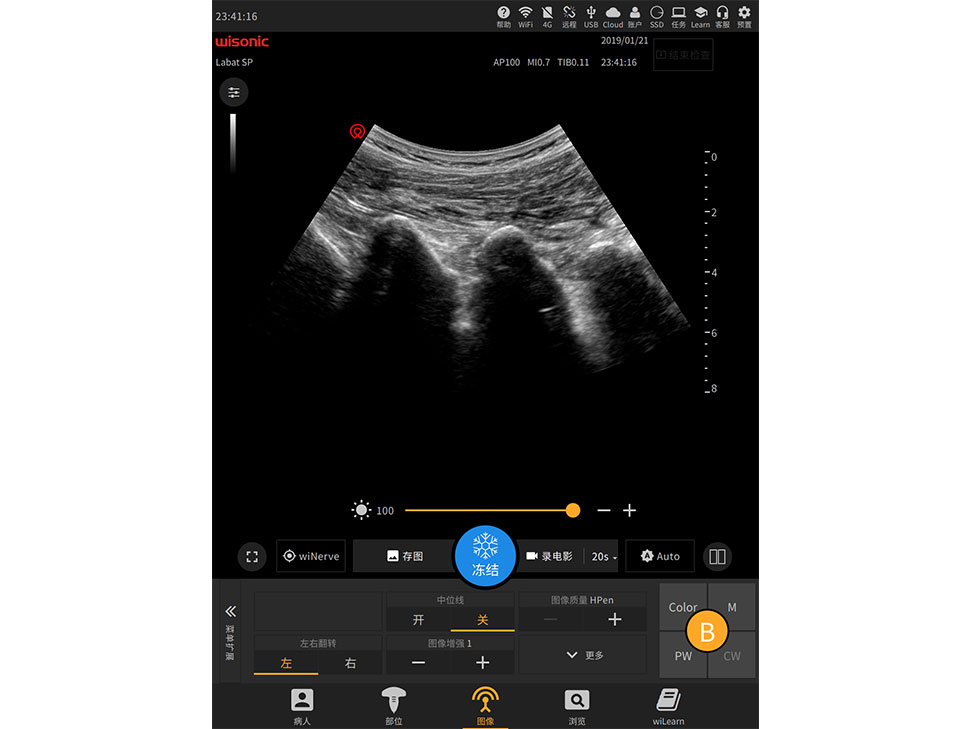

Overview

Videos

Images

Documents